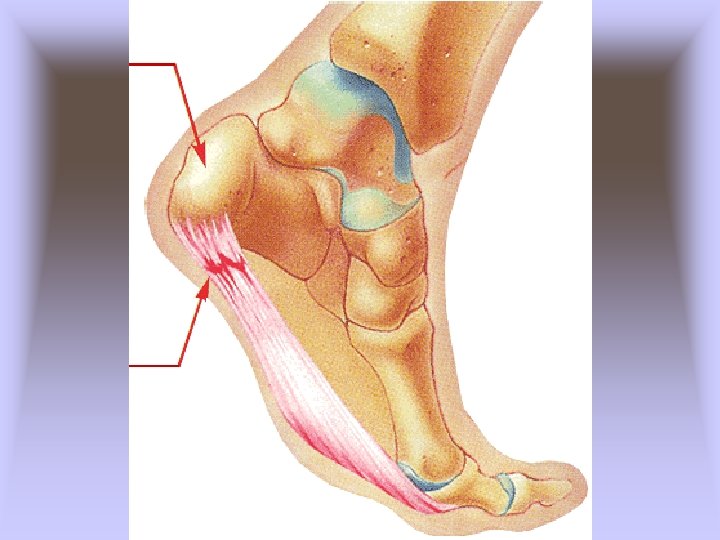

• Retrocalcaneal Bursitis (Pump Bump) – Cause of Injury • Caused by inflammation of bursa beneath Achilles tendon • Result of pressure and rubbing of shoe heel counter of a shoe • Chronic condition that develops over time and may take extensive time to resolve, exostosis (pump bump) may develop • Must differentiate from Sever’s disease

– Sign and Symptoms • Signs of inflammation • Tender, palpable bump on calcaneous • Pain w/palpation superior and anterior to Achilles insertion, swelling on both sides of the heel cord – Care • Routine stretching of Achilles, heel lifts to reduce stress, donut pad to reduce pressure • Select different footwear that results in increasing or decreasing height of heel counter.